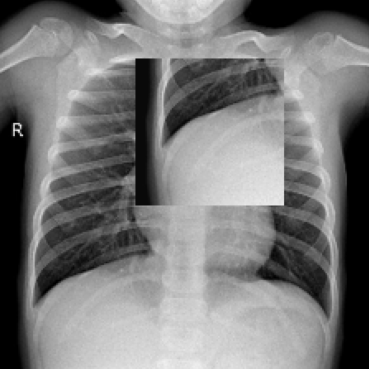

We leverage the position prior of the chest X-ray to introduce a Position-guided Prompt learning method for chest X-ray Anomaly Detection (PPAD). Specifically, we divide the image into four sections: left lung, right lung, upper lung, and lower lung. Taking the left lung as an example (see Fig. 1), we initiate the text input with “left lung”. For the image input, we focus on the left lung within the image, masking the right lung with a binary mask . We mask the right lung to prevent it from influencing the result. Subsequently, we introduce learnable text prompt and image prompt . The text input is converted into token embeddings by the text patch embed module. We separate it into position prompt embeddings and class embeddings . The learnable text prompt is inserted between and . The text input of the text encoder emerges as a combination, denoted as:

The impact of position guidance is visualized through the Class Activation Mapping (CAM) in Fig. 3. In the first row, the entire lung view fails to detect anomalies in the left region. However, specific views focused on the left, upper, and lower sections of the lung successfully identify these anomalies. In the second row, the left lung view detects anomalies that are missed in the entire lung view. These outcomes indicate the importance of utilizing diverse position prompts.